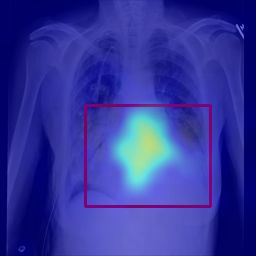

Deployments of artificial intelligence in medical diagnostics mandate not just accuracy and efficacy but also trust, emphasizing the need for explainability in machine decisions. The recent trend in automated medical image diagnostics leans towards the deployment of Transformer-based architectures, credited to their impressive capabilities. Since the self-attention feature of transformers contributes towards identifying crucial regions during the classification process, they enhance the trustability of the methods. However, the complex intricacies of these attention mechanisms may fall short of effectively pinpointing the regions of interest directly influencing AI decisions. Our research endeavors to innovate a unique attention block that underscores the correlation between 'regions' rather than 'pixels'. To address this challenge, we introduce an innovative system grounded in prototype learning, featuring an advanced self-attention mechanism that goes beyond conventional ad-hoc visual explanation techniques by offering comprehensible visual insights. A combined quantitative and qualitative methodological approach was used to demonstrate the effectiveness of the proposed method on the large-scale NIH chest X-ray dataset. Experimental results showed that our proposed method offers a promising direction for explainability, which can lead to the development of more trustable systems, which can facilitate easier and rapid adoption of such technology into routine clinics. The code is available at www.github.com/NUBagcilab/r2r_proto.